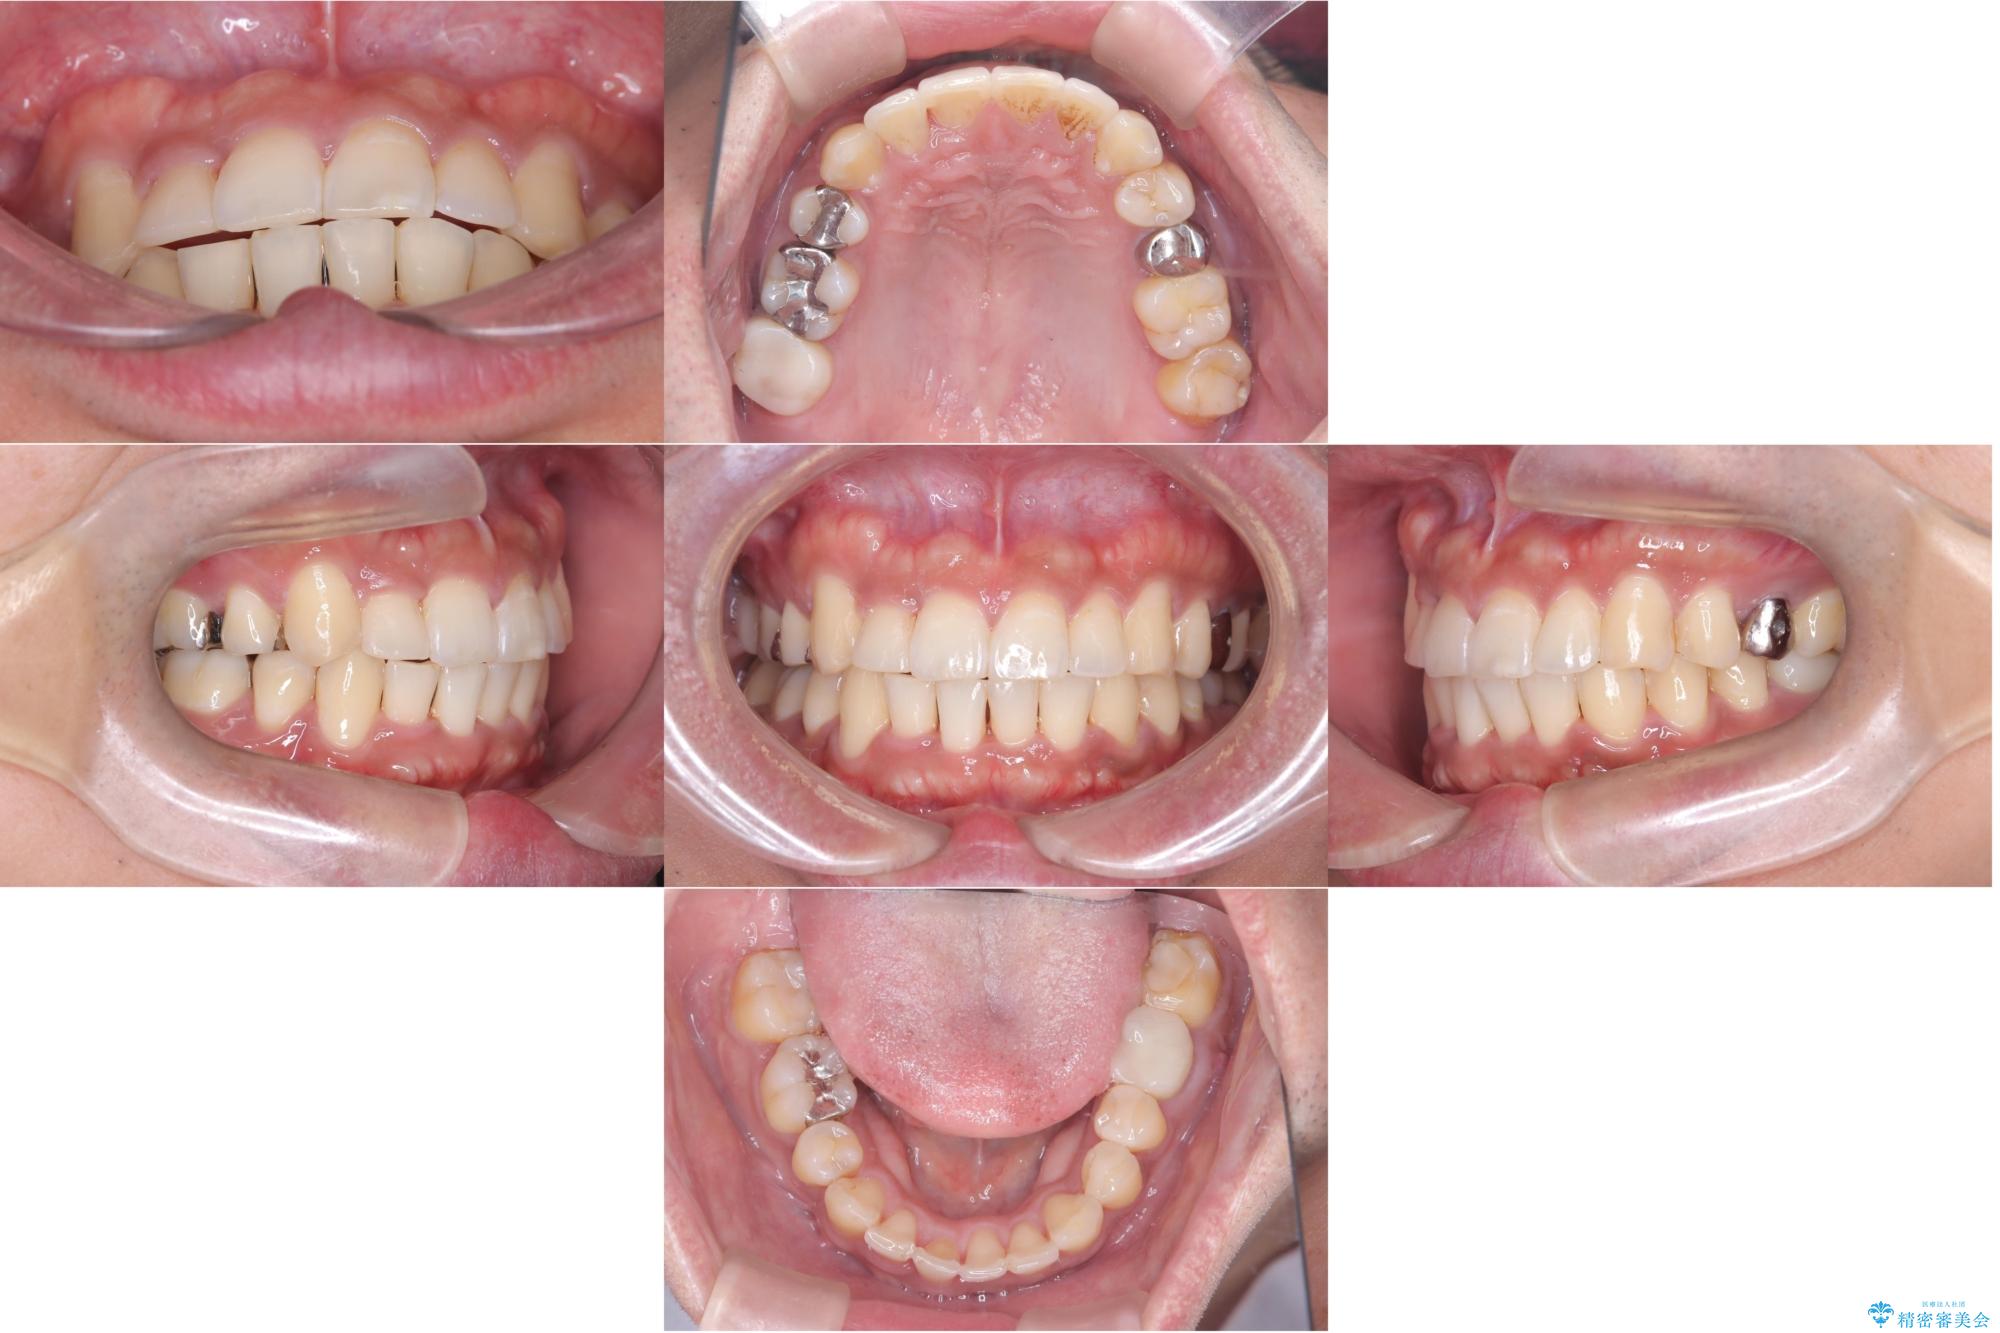

【ワイヤー矯正】八重歯と下の歯の凸凹を治したい

- 主訴:右上の八重歯と、下の歯の凸凹を治したい

上顎右側第一小臼歯と下顎右側第一小臼歯を抜歯しワイヤー矯正を行いました。

右側2級、左側1関係だったため、右側上下第一小臼歯を抜歯し、ワイヤー矯正を行いました。

期間:2年6カ月